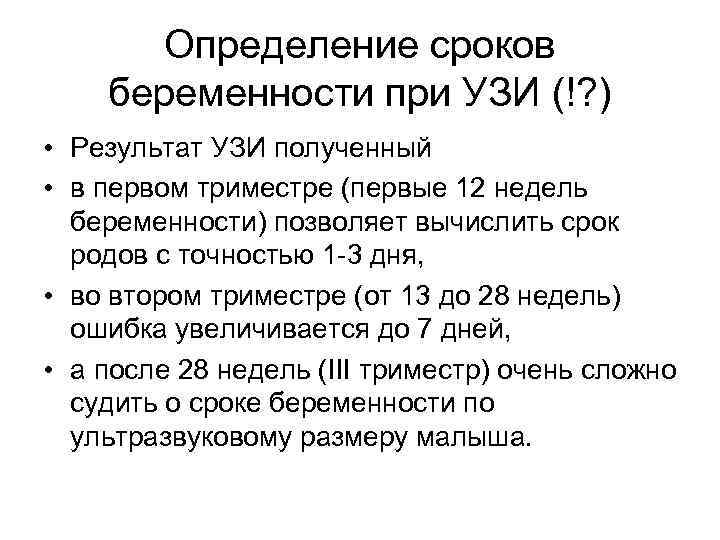

Определение сроков беременности при УЗИ (!? ) • Результат УЗИ полученный • в первом триместре (первые 12 недель беременности) позволяет вычислить срок родов с точностью 1 -3 дня, • во втором триместре (от 13 до 28 недель) ошибка увеличивается до 7 дней, • а после 28 недель (III триместр) очень сложно судить о сроке беременности по ультразвуковому размеру малыша.

Определение сроков беременности при УЗИ (!? ) • Результат УЗИ полученный • в первом триместре (первые 12 недель беременности) позволяет вычислить срок родов с точностью 1 -3 дня, • во втором триместре (от 13 до 28 недель) ошибка увеличивается до 7 дней, • а после 28 недель (III триместр) очень сложно судить о сроке беременности по ультразвуковому размеру малыша.